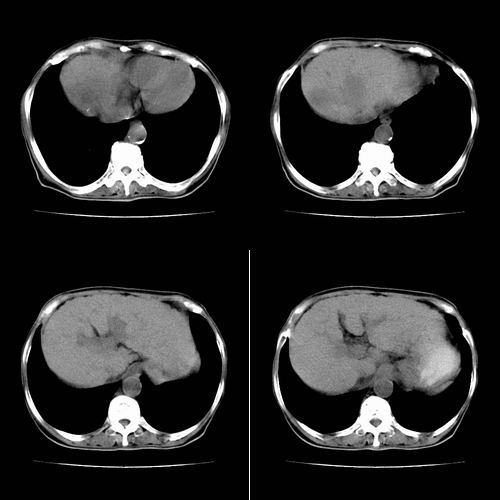

患者 女性 58岁,家族有乙肝病史,(并姊妹中已有3人确诊肝癌,真是不幸!乙肝病毒真是害死人!)近期明显消瘦,乏力,右上腹疼痛.行ct结果非常典型,请诸位老师会诊!

图片非常漂亮!肝内病灶符合较典型肝癌的强化方式,速升速降,其内可见坏死,腹膜后示肿大淋巴结融合成团,包绕腹主动脉、腹腔干动脉、肠系膜动脉。右肾小囊性病灶,未见明显强化。

诊断:肝癌并腹膜后淋巴结转移。

符合右肾囊肿

地一个图是双期扫描`~~~~动脉期肿瘤强化~~静脉期肝实质强化`~肿瘤不强化`~很典型是个肝ca~~

肝脏80%左右有静脉供血~~~所以地一个强化肯定不是肝实质~~~平扫有个低密度的`~结合临床可以肯定